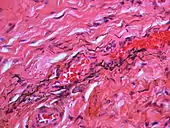

Over time, the amalgam particles embedded in the soft tissues corrode.[5]: 183 Macrophages take up the exogenous particles, and the silver in amalgam leads to staining of collagen fibers.[5]: 183

If necessary, the diagnosis can be confirmed histologically by excisional biopsy, which excludes nevi and melanomas.[3]: 138 If a biopsy is taken, the histopathologic appearance is:[1]

- Pigmented fragments of metal within connective tissue

- Staining of reticulin fibers with silver salts

- A scattered arrangement of large, dark, solid fragments or a fine, black or dark brown granules

- Large particles may be surrounded by chronically inflamed fibrous tissue

- Smaller particles surrounded by more significant inflammation, which may be granulomatous or a mixture of lymphocytes and plasma cells